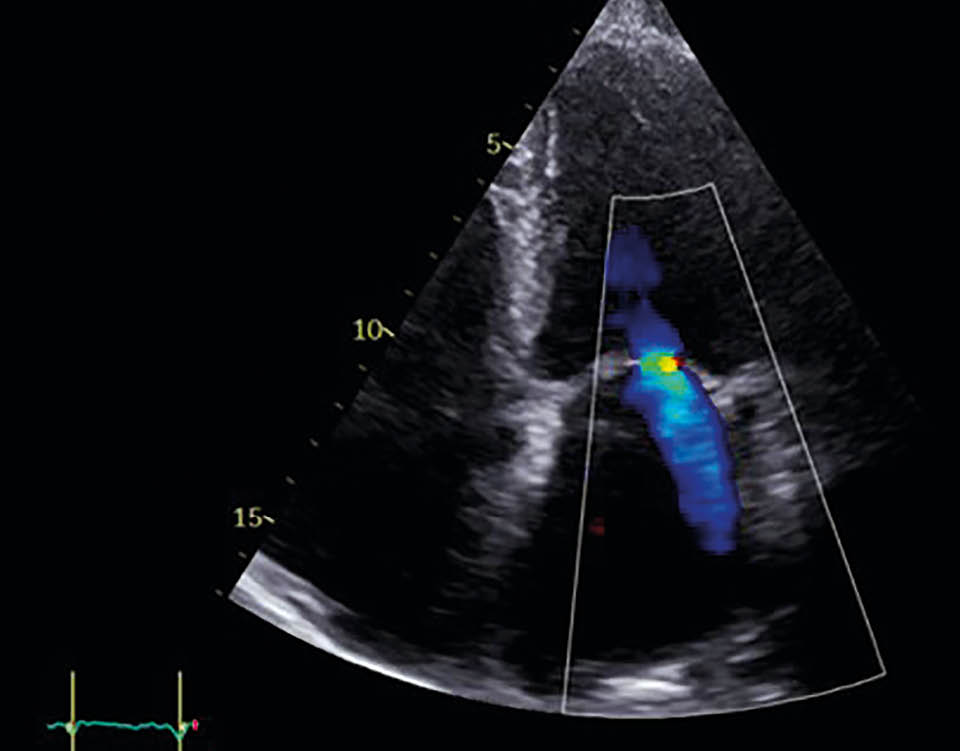

Abbildung 3d: Mitralklappeninsuffizienz in TTE

nach der Behandlung

Ergebnisse

Postinterventionell zeigte sich echokardiografisch eine Reduktion der MI auf Grad 1 mit deutlicher Abnahme des EROA auf 0,1 cm2. Die Patientin berichtete bereits am ersten postinterventionellen Tag über eine deutliche Besserung der Dyspnoe. Die Entlassung erfolgte am zweiten postprozeduralen Tag unter stabilen hämodynamischen Verhältnissen. Die strukturelle Nachsorge ist über den niedergelassenen Kardiologen in enger Zusammenarbeit mit der kardiologischen Klinik organisiert (TTE-Kontrollen nach 1, 3 und 6 Monaten, Laborparameter, 6-Minuten-Gehtest [6MWT]).